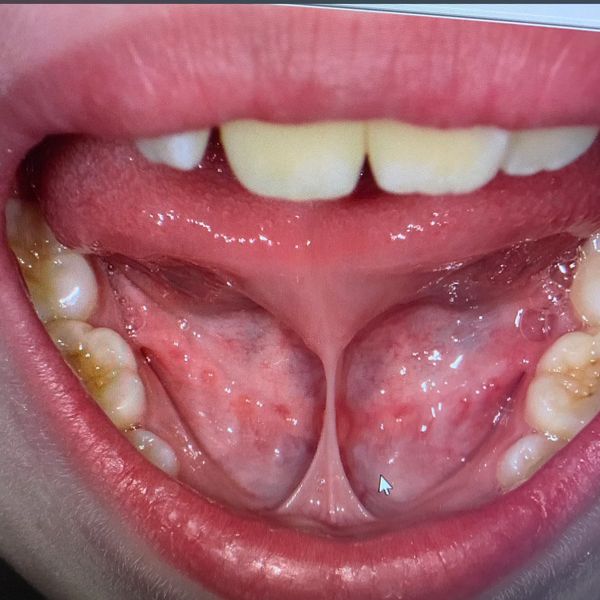

Whether you are struggling with an infant who is experiencing feeding issues, slow weight gain, reflux and/or colic symptoms. Or your older child who dealing with sleep concerns like snoring or grinding their teeth, speech impediments or a picky eater. Having a Functional Assessment early in life to screen for tethered oral tissues (tongue tie) can be life changing and prevent many bad habits associated with oral restrictions from forming. As an IBCLC & Orofacial Myologist, Sherrie has the experience and expertise to develop an indivualized care plan specific to your child’s needs.

Maybe your infant already had a release with another provider and is still struggling or no aftercare instructions were given. They may benefit from Oral Habilitation, contact Sherrie at info@sherriepruitt.com to see if this therapy could be beneficial to your little one.

Preparation is key, both mentally and physically and is just as important as the after care. This care is never one size fits all, Sherrie ensures pre and post operative care is tailored to fit each child’s individual needs. For some, more extensive therapy is required, inquire with Sherrie for pricing and scheduling of these therapies.